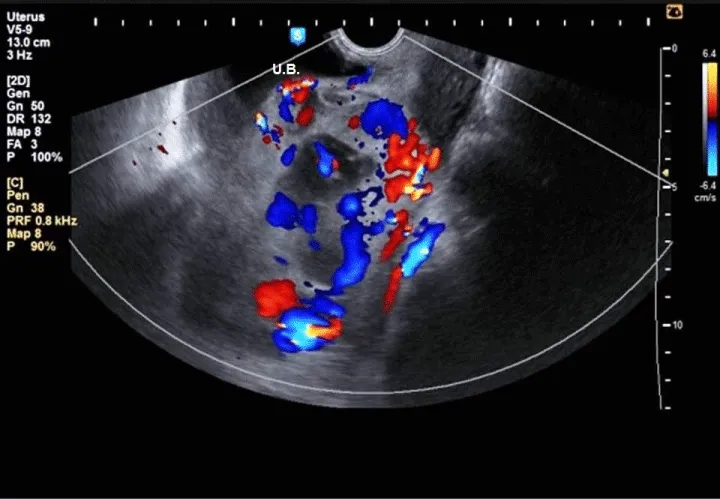

A 26 years old lady who had previously given birth to two children by cesarean sections (CS) and an exploratory laparotomy 10 years before marriage for removal of a complicated ovarian cyst. She was presented with a 2 weeks missed period where trans-vaginal ultrasound revealed a 5 weeks single intrauterine gestational sac equipping the isthmo-cervical portion of the uterus almost at site of the previous caesarean section scar with empty uterine cavity Figure 1. Two weeks later, the sac was still in the same site with positive fetal pulsation and another two weeks later, she started to develop mild vaginal bleeding with mild lower abdominal pain where ultrasound revealed healthy pregnancy with retro-chorionic hematoma 5 × 4 cm. 3 Dimension Ultrasound Doppler revealed the absence of demarcation line between trophoblast and myometrium with the trophoblast reaching as far as the serosa of the peritoneum covering the urinary bladder Figure 2. Termination of pregnancy by laparotomy was performed where the urinary bladder was found completely adherent to the uterus with high vascularity and varicosity covering this area. Bilateral uterine arteries ligation was done before opening the uterus. Small bladder injury occurred during dissection of the urinary bladder, which was sutured later on in double layer. On uterine incision, chorionic tissue was found bulging from site of the scar Figure 3 with a small part adherent to the uterine wall, excision of this part and closure of uterus was done after taking 3 U-shaped sutures in the lower part of the uterus. Patient received 2 units of blood and 2 units of plasma.

This diagnosis of placenta accreta (PA) is difficult during the first trimester, the currently known prenatal sonographic characteristics of PA low-lying gestational sac with diffuse dilatation of intra-placental vessels (lacunae). Also, PA is suspected if part of the lining of the gestational sac is embedded in the previous CS scar with an irregular decidual layer and thinning of the underlying uterine wall [5,6].